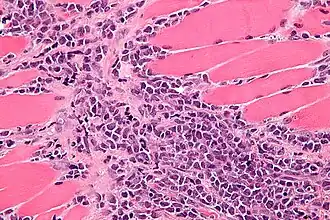

Микрофотография миелоидной саркомы в ткани мышцы

Миелоидная саркома (устаревшие названия «хлорома», «хлоролейкоз», «гранулоцитарная саркома», «гранулосаркома»,[2]:744 «экстрамедуллярная миелоидная ткань/опухоль»), — это солидная злокачественная опухоль, состоящая из незрелых клеток белого кровяного ростка костного мозга, так называемых миелобластов, аналогичных тем, которые вызывают острый миелоидный лейкоз.[3]. Другими словами, миелоидная саркома («хлорома», «гранулоцитома») — это одно из экстрамедуллярных (то есть вне-костномозговых) проявлений острого миелоидного лейкоза. То есть это скопление лейкозных клеток, характерных для острого миелоидного лейкоза, где-либо за пределами костного мозга и крови.